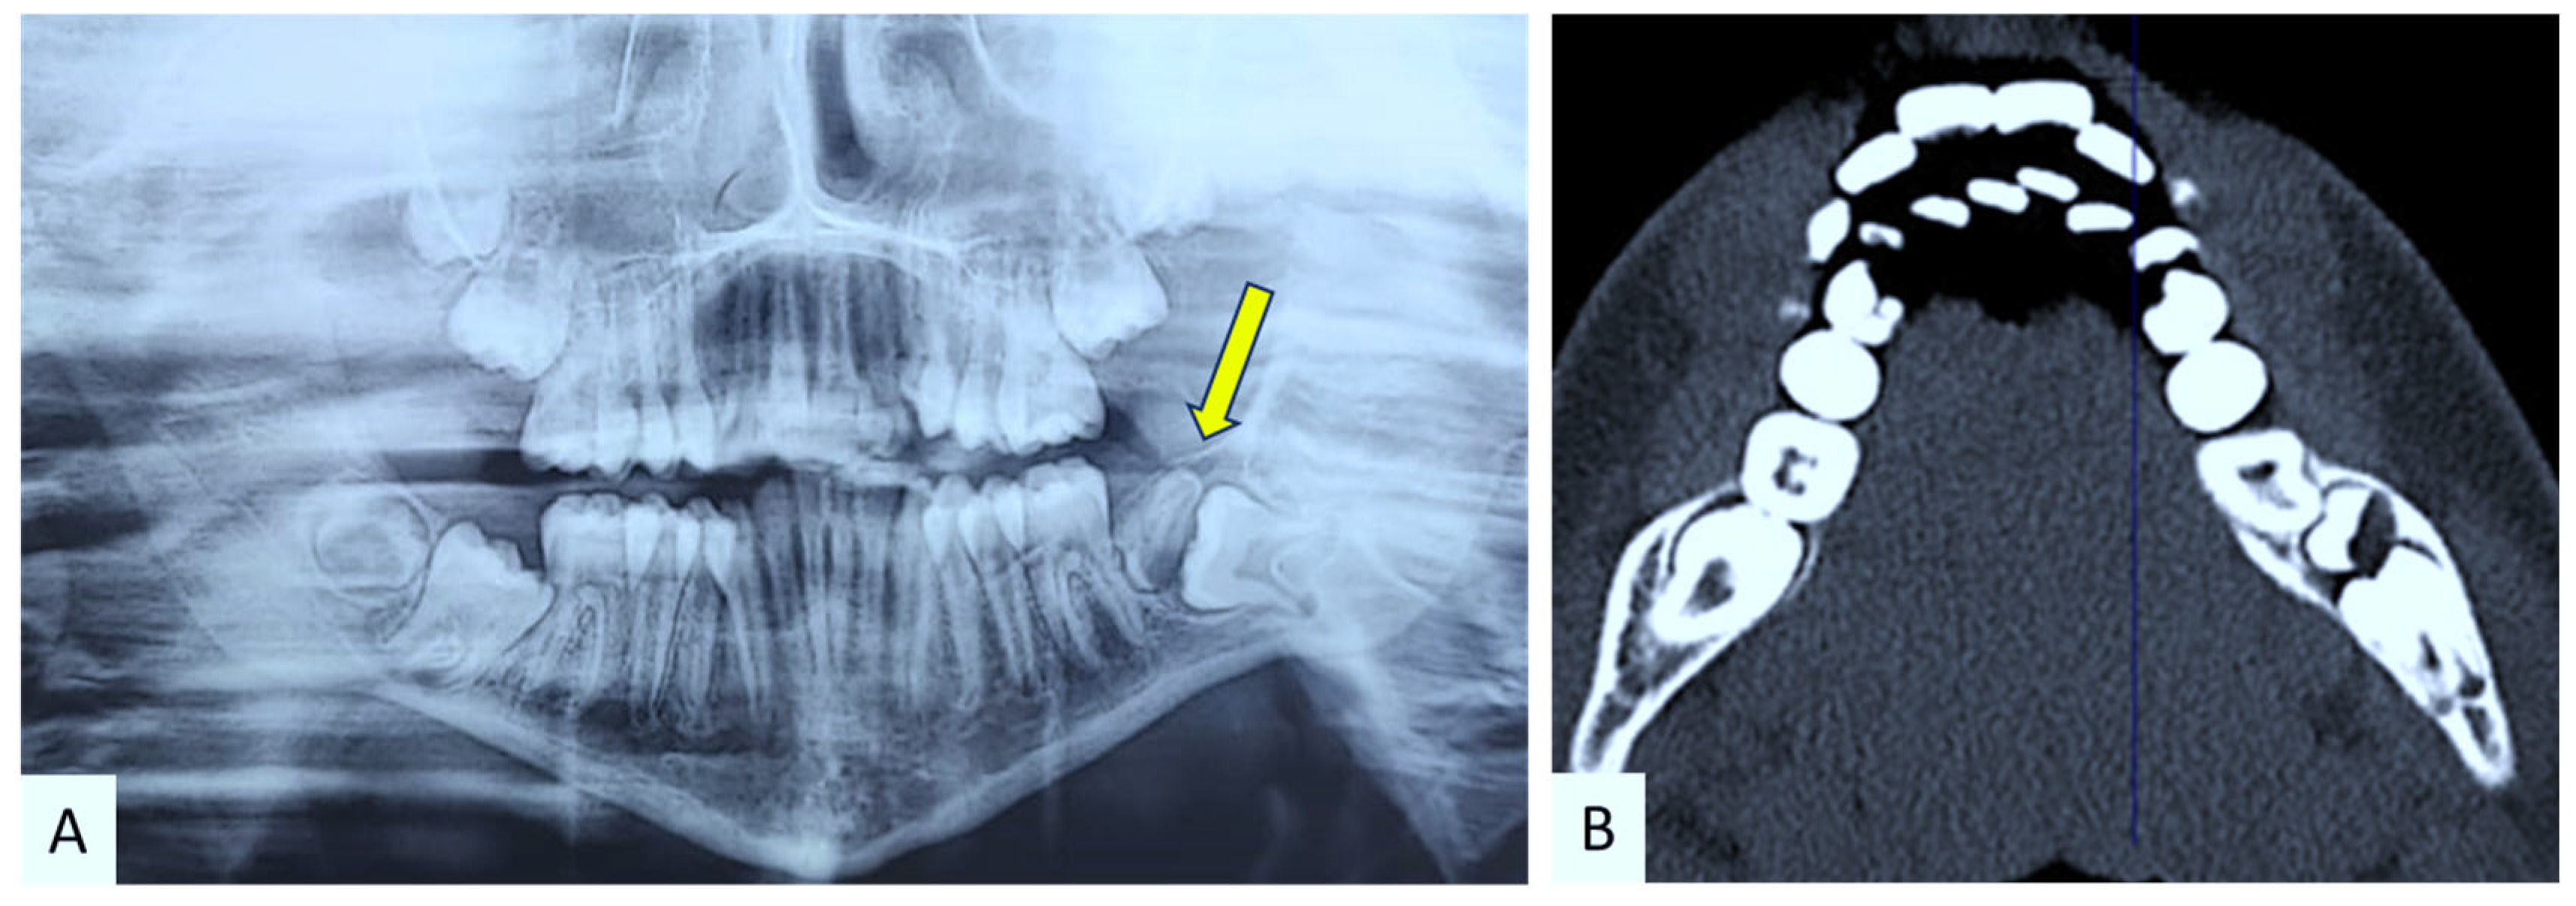

2.1. Case Presentation